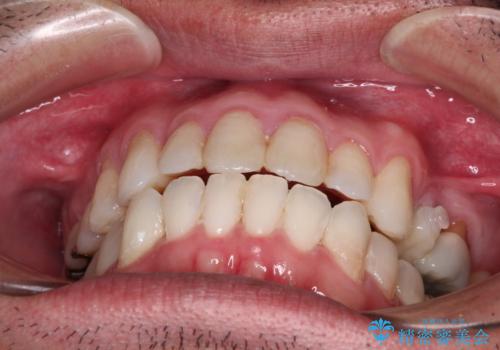

内側に転位した歯とボロボロのむし歯 インビザラインによる矯正治療とむし歯治療

- ボロボロのむし歯とデコボコの歯列を気にして来院された患者様です。

ボロボロとなっていた歯は抜歯が必要な状態でしたが、舌側転位している歯を移動させることで抜歯スペースを埋めることができるため、矯正治療により歯列を整えることとしました。

舌側転位の改善にインビザラインを用いるのはやや難易度が高くなりますが、前歯部のデコボコは軽度であったため、インビザラインによる矯正治療を行うこととしました。